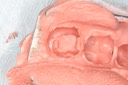

Gary Umeda #2-3 prep